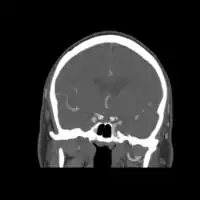

Carotid artery dissection

Dissection of the carotid artery on ultrasound